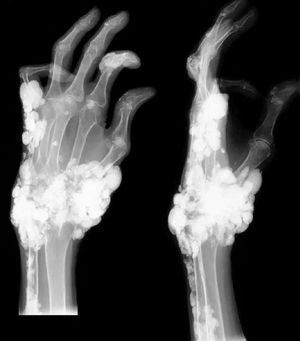

Oh that? That’s just a tumoral calcinosis spread throughout his claw-hand! This is a rare hereditary condition that causes metabolic dysfunction of phosphate regulation and is associated with development of massive calcium depositions in the soft tissue in periarticular location (around joints). Patients present with lumps adjacent to joints that are painless in most cases and localized swelling with tenderness. The underlying bone isn’t affected. The picture above shows a typical appearance of tumoral calcinosis on plain radiographs with amorphous and multilobulated ("cloud-like") calcification located around the joints. This disease should always be differentiated from calcinosis as a result of chronic renal failure that typically has the very same radiologic appearance and diagnosis must be based on vitamin D levels, kidney functional parameters (GFR), and history of renal failure or long term dialysis. Complete surgical excision is advised with symptomatic lesions, otherwise observation is sufficient. Photo by @medizzy app.